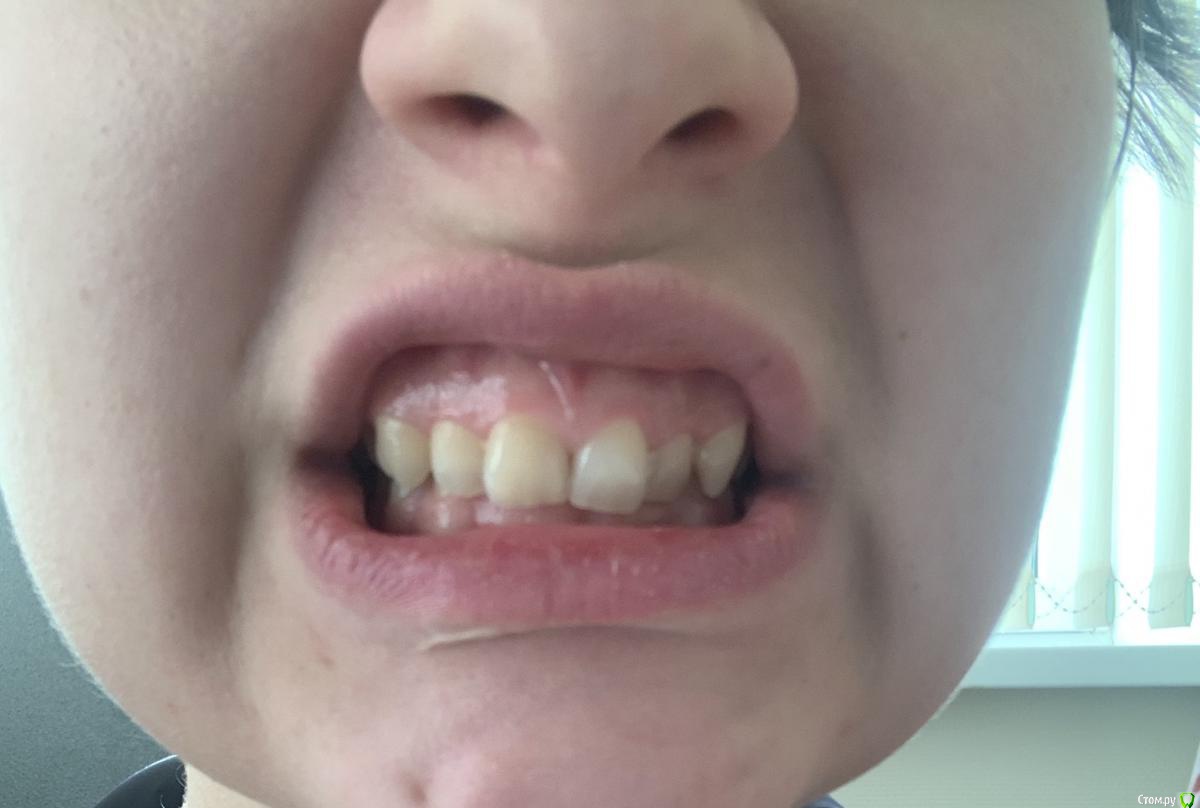

marionn Опубликовано 10 февраля, 2020 Поделиться Опубликовано 10 февраля, 2020 Добрый день, женщина, 31 годЧто беспокоит: на настоящий момент у меня ничего не болит. но на протяжении уже лет 5-6 в течение трех месяцев на внутренней поверхности передних нижних зубов образовывается зубной камень, каждый год посещаю стоматолога, и вот уже три года подряд мой стоматолог говорит, что мне необходима обязательная установка брекетов, ввиду того, что зубы стоят слишком скученно, что может привести к пародонтозу (или пародонтиту, не уверена в точности передаваемого) и что кариес на зубах, которых в основном образовывается в местах соприкосновения зубов друг с другом, возникает из-за прикуса. Также мой стоматолог сказала, что верхние зубы давят на нижние, а нижние на верхние из-за неправильного прикуса и таким образом еще больше деформируется челюсть, прикус и так далее. В настоящий момент у меня имеется панорамный снимок зубов, который я делала 2 года назад. Могли бы вы сказать, есть ли острая необходимость в брекетах и коррекции прикуса? Ссылка на комментарий